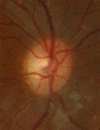

Optic neuritis is an inflammation of the optic nerve and may be related to different systemic conditions. The clinical presentation of this pathology usually includes sudden loss of visual acuity (VA) which may be unilateral or bilateral, visual field restriction, pain with eye movements, dyschromatopsia, a relative afferent pupillary defect and optic disk swelling. Optic neuritis in children has specific clinical features and a better prognosis than in adulthood. Although usually appears an underlying viral disease, the main concern for practitioners is the relationship of optic neuritis with multiple sclerosis. In addition to the classical techniques as magnetic resonance imaging (MRI), current tendencies of diagnosis for eye practitioners include new imaging devices as optical coherence tomography (OCT), useful to show a thinning of the retinal fibers layer (RFL) after the inflammatory episode. Regarding the management of these patients, short-term intravenous steroid dosages seem to be the best option to treat acute attacks characterized by a very poor bilateral VA.